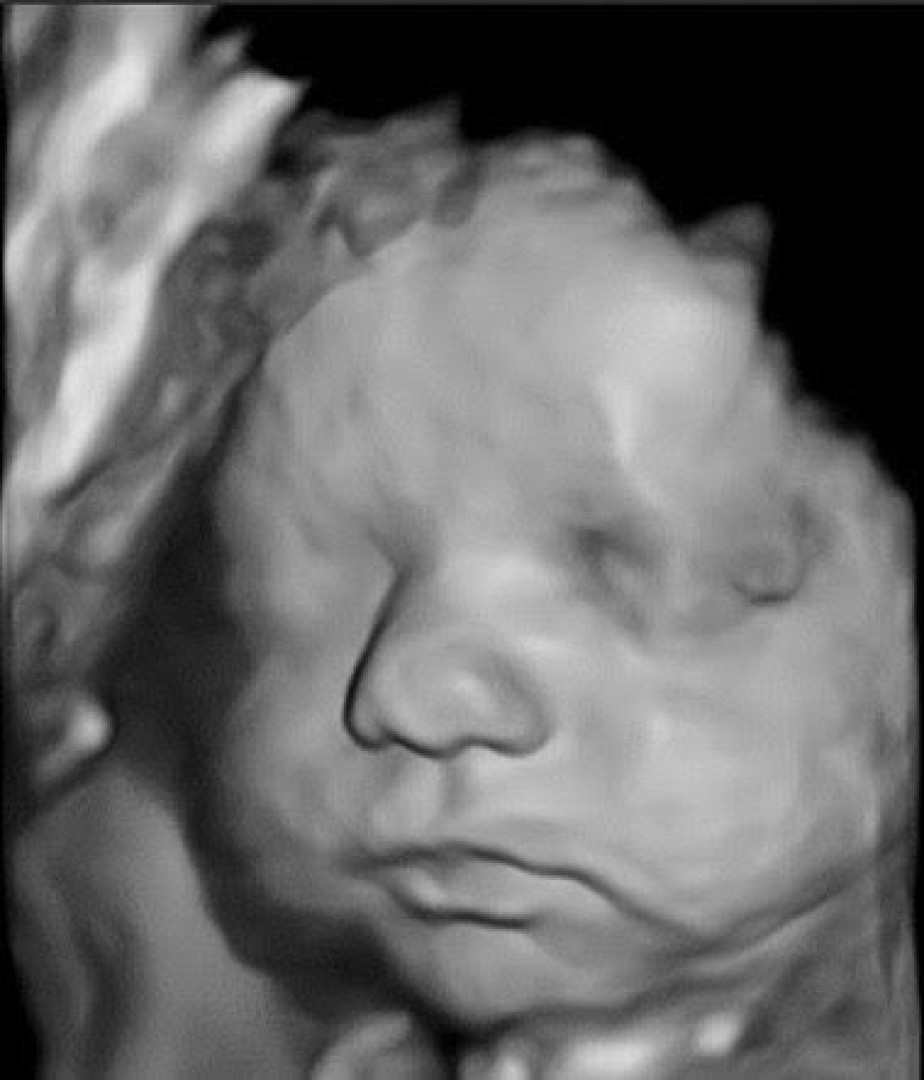

Moja kariera zawodowa związana jest z położnictwem i ginekologią. Problematyka ciąży jest mi szczególnie bliska, a diagnostyka prenatalna i ultrasonografia …

Moja kariera zawodowa związana jest z położnictwem i ginekologią. Problematyka ciąży jest mi szczególnie bliska, a diagnostyka prenatalna i ultrasonografia są nie tylko ważną częścią mojej codziennej pracy zawodowej, ale jedną z pasji.

Ukoronowaniem zainteresowań była rozprawa doktorska poświęcona ocenie układu krążenia matczynego i płodowego w przypadkach ciąży powikłanej nadciśnieniem tętniczym (2008) oraz akredytacje The Fetal Medicine Foundation (FMF)- najważniejszej europejskiej instytucji certyfikującej i nadzorującej specjalistów zajmujących się diagnostyką prenatalną. Posiadam certyfkaty umiejętności Sekcji Ultrasonografii Polskiego Towarzystwa Ginekologicznego w zakresie Diagnostyki Prenatalnej oraz badań serca płodu oraz licencje Fetal Medicine Foundation (FMF) dot. przeprowadzania ultrasonograficznych badań płodu między 11 a 14 tygodniem ciąży, 20-22 tygodniem ciąży, badań serca płodu czy badań dopplerowskich w ciąży.

Możliwość połączenia świata perinatologii, diagnostyki prenatalnej i kardiologii prenatalnej są niezwykle cenne i gwarantują kompleksowość konsultacji.